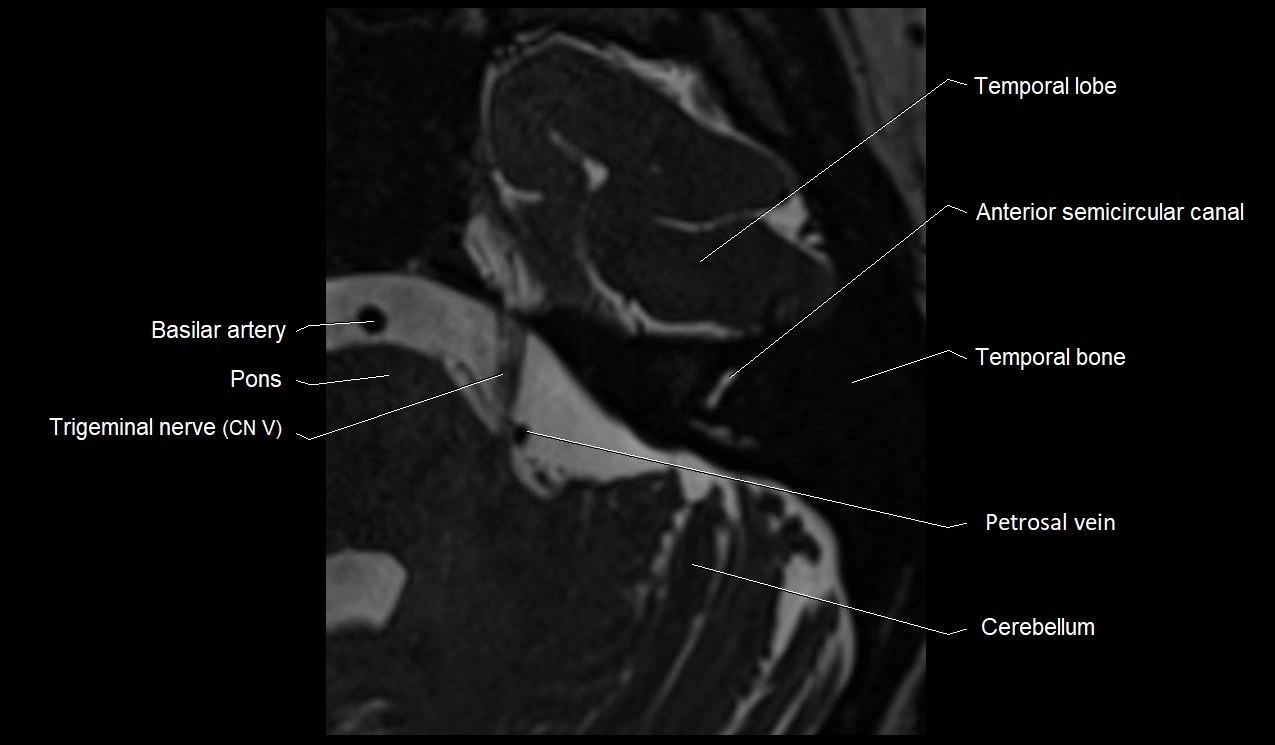

TEST YOURSELF